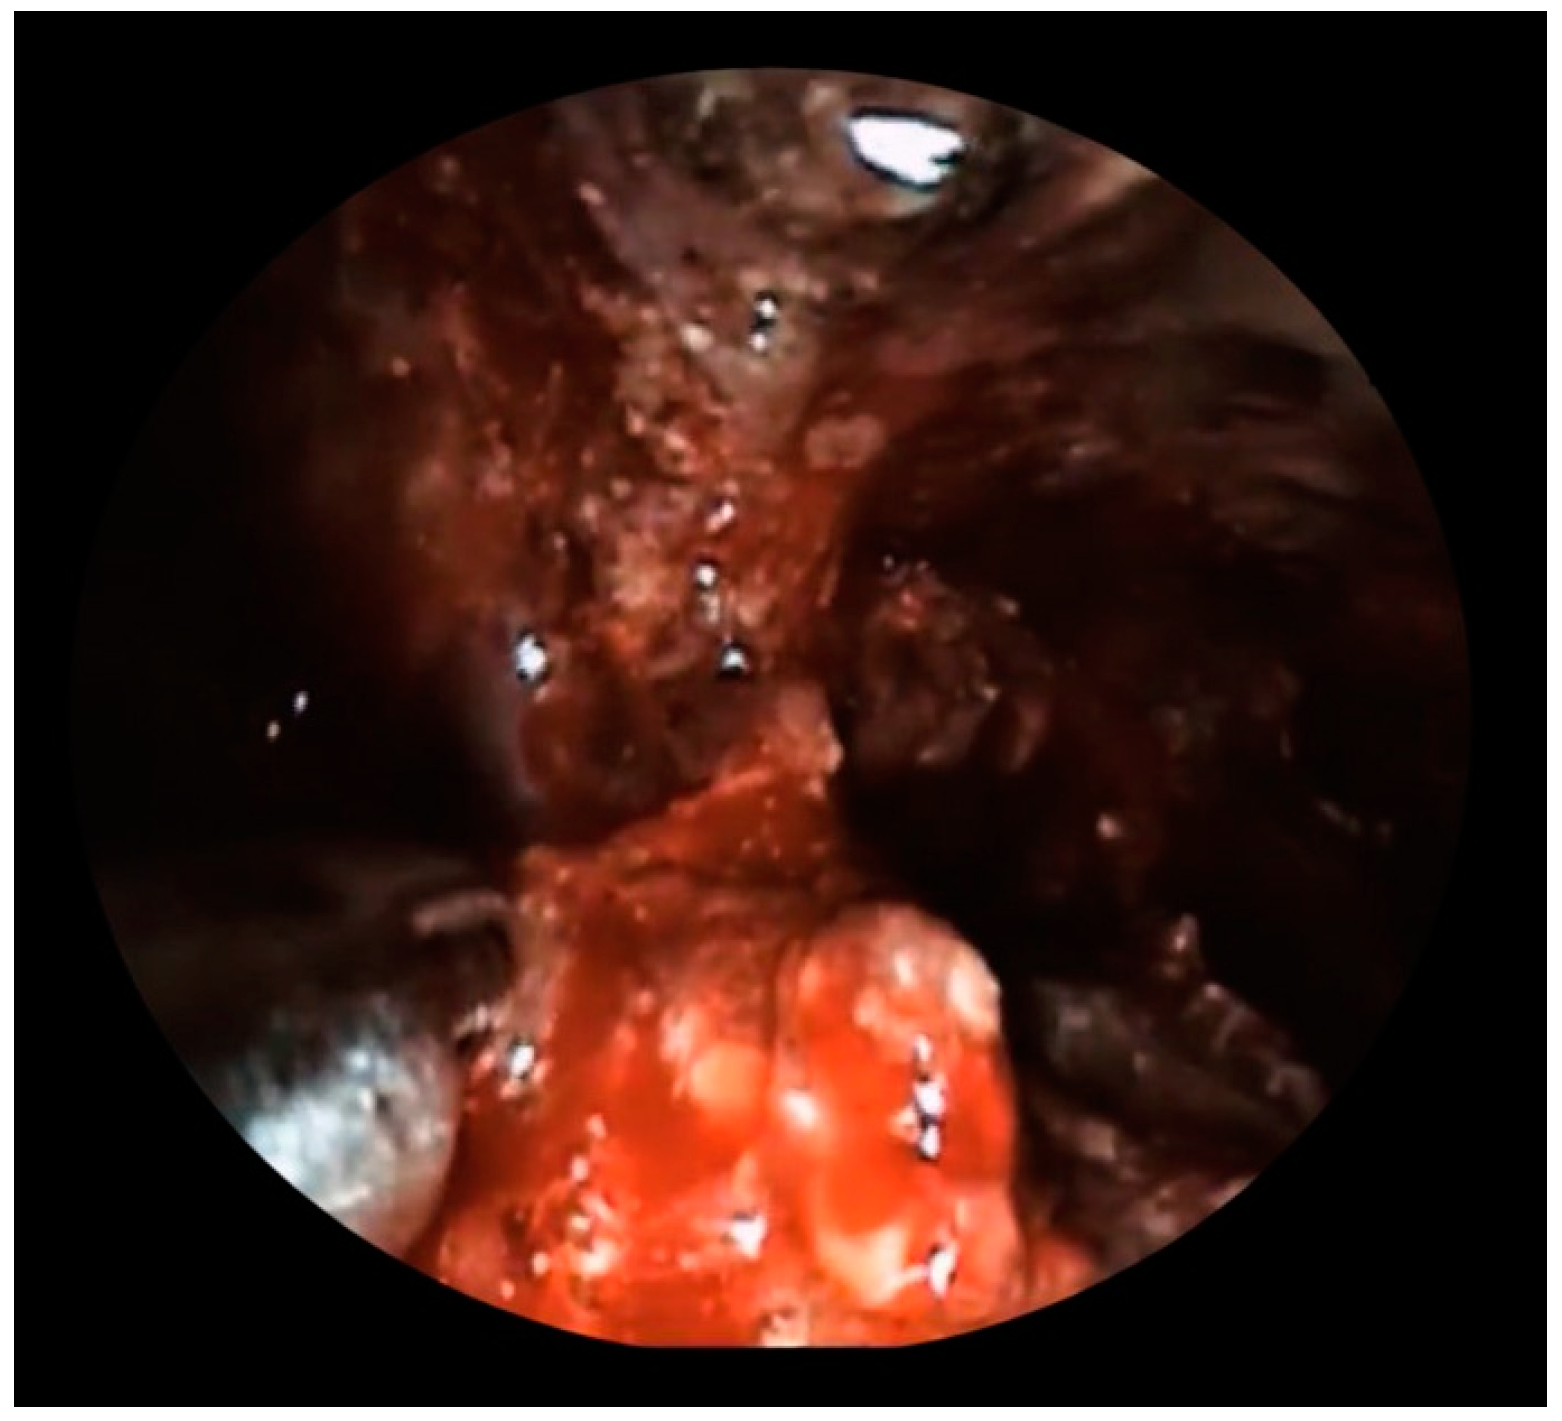

Figure 2.

Fluoroscopic view of selective cannulation of splenic artery with a catheter inserted through the common femoral artery.